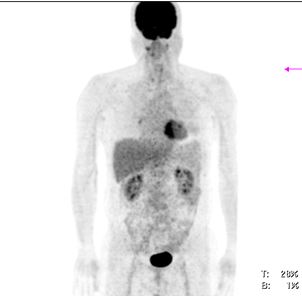

v Bệnh nhân được đánh giá đáp ứng hoàn toàn, tiếp tục theo dõi và khám định kỳ. Hiện tại sau điều trị 6 năm bệnh nhân ổn định. Hình ảnh PET/CT không thấy tăng hấp thu FDG bất thường tại cơ quan bộ phận nào khác của cơ thể.

Hình 3: Hình ảnh PET/CT sau điều trị 6 năm không thấy tăng hấp thu FDG bất thường tại cơ quan bộ phận nào khác của cơ thể.

Hình 6: Sau điều trị 6 năm: hình ảnh chụp PET/CT sau điều trị cho thấy khối hạch cổ trái tan biến hoàn toàn, không thấy tăng hấp thu FDG tại cơ quan bộ phận khác của cơ thể.